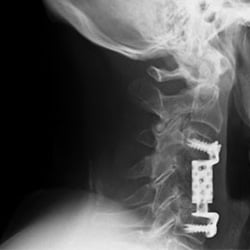

The image on the left is detail of an x-ray image created after cervical spine surgery. Postsurgically, it was crucial to assess the adequate position of the vertebral body replacement.